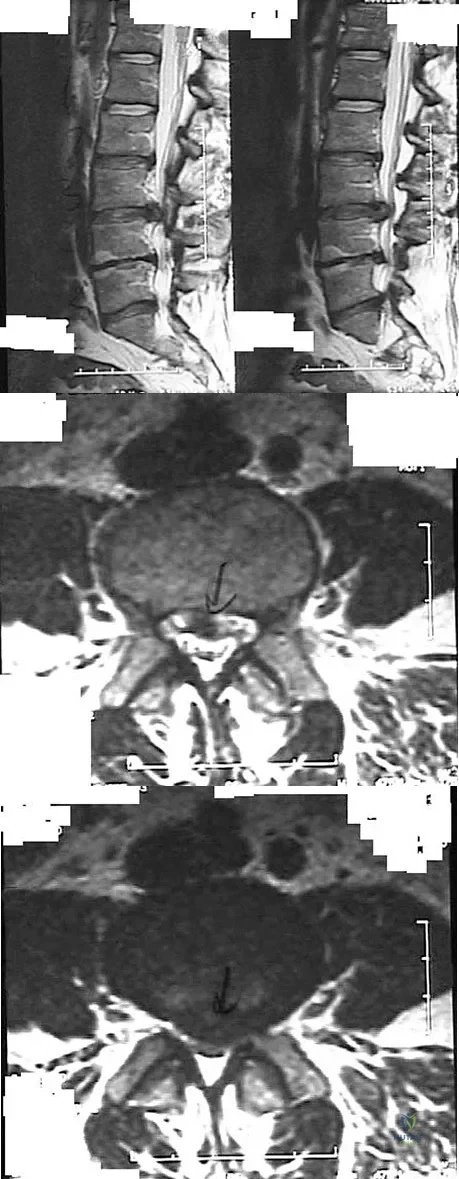

Figures 28a through 28c show the MRI scans of a 30-year-old woman who weighs 290 lb and has low back and left leg pain. She also reports frequent urinary dribbling, which her gynecologist has advised her may be related to obesity. Examination will most likely reveal

Explanation

Examination of a 34-year-old man who has had left leg pain for the past 6 weeks reveals minimal weakness of the left extensor hallucis longus and normal ankle jerk and patellar reflexes. Figure 33 shows an axial MRI scan of the L4-5 disk. Based on these findings, the MRI scan results are consistent with compression of the

Explanation